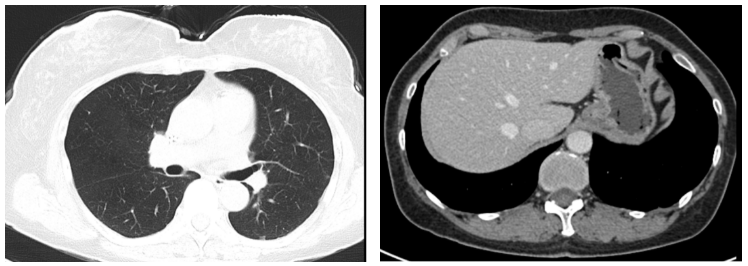

两个疗程后复查CT:右乳Ca伴右腋下淋巴结M(较前相仿),伴两肺弥漫性转移(图3,较前缓解),肝脏转移灶消失(图3)。胸腰椎转移灶,较前相仿。疗效评价PR。

图3. 2019.03两肺转移灶(左图),肝左叶转移灶(右图)